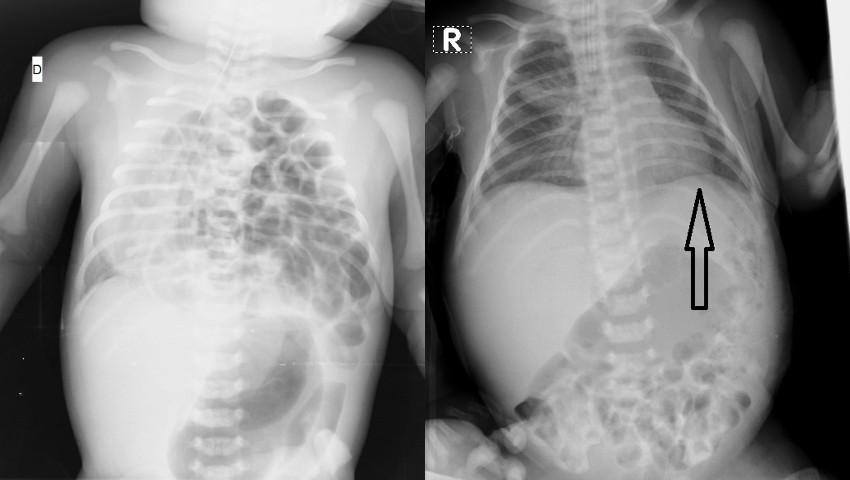

Înainte de operație: se observă toate ansele intestinului prezente în cutia toracică a bebelușului.

La examenul antenatal, la ecografie de 20 săptămâni de gestaţie, bebelușului i-a fost suspectată o anomalie gravă - hernia diafragmatică pe stânga, cu hipoplazie pulmonară bilaterală. Cazul s-a aflat la evidenta medicilor specialiști. Copilul s-a născut la termen prin operaţie cezariană, cu greutatea de 4.1 kg. Postnatal, diagnosticul a fost confirmat prin examinări imagistice, constatându-se amplasarea în torace a anselor intestinului subţire şi gros cu deplasarea contralaterală a organelor mediastinului (dextropoziţia cordului) și o compresie majoră a plămânului hipoplaziat.